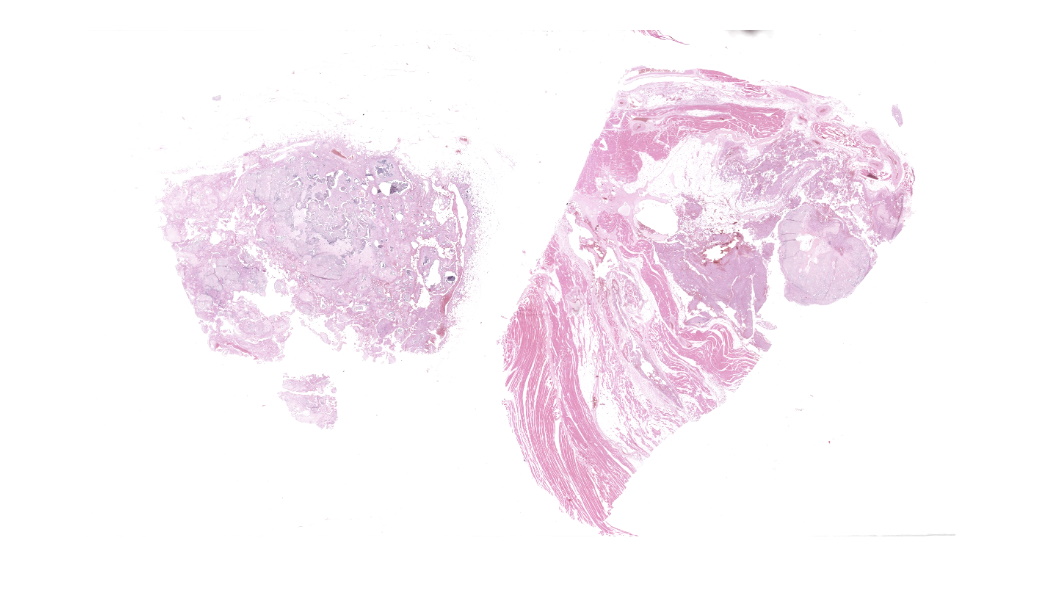

The affected skeletal muscle and subcutis were infiltrated and expanded by abundant, irregular, globoid amphophilic to basophilic material, consistent with mineralization. This mineralized material was surrounded by extensive fibrous connective tissue proliferation (fibrosis), admixed with numerous macrophages, lymphocytes, and fewer multinucleated giant cells containing phagocytosed mineral material. Scattered throughout the mass, rare foci of osteoid formation were observed, characterized by a low number of empty lacunae and necrotic osteoids undergoing remodeling. Multifocally within the mineralized soft tissue lesions, multiple tortuous blood vessels with thickened tunica media were observed. Additionally, there were areas of extensive hemorrhage, neovascularization, and granulation tissue formation infiltrating and replacing the surrounding adipose tissue.

Skeletal muscle: Granulomatous myositis and steatitis with soft tissue mineralization, chronic, focally extensive, severe, with fibrosis and rare osseous metaplasia.

Subcutaneous fat and skeletal muscle: Mineralization, chronic, focally extensive, severe, with granulomatous inflammation and osseous metaplasia.